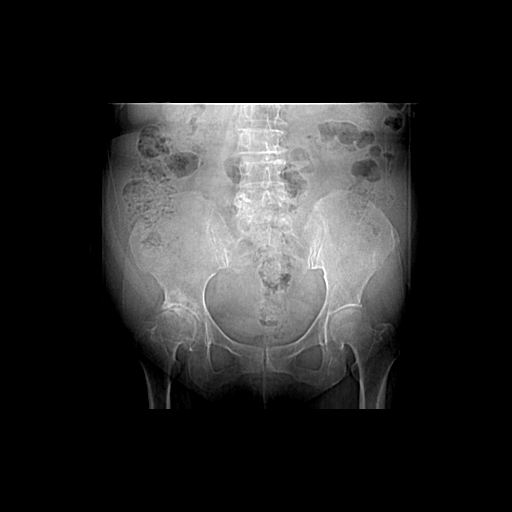

以下是引用王显瑞在2009-4-23 16:45:00的发言:[br]考虑股骨颈陈旧性骨折,股骨头缺血型坏死

以下是引用余辉在2009-4-23 17:08:00的发言:[br]考虑右髋关节退行性变.股骨颈改变考虑陈旧性骨折可能,股骨头顶部关节面下似有透亮区,股骨头皮质环增厚,考虑有股骨头坏死